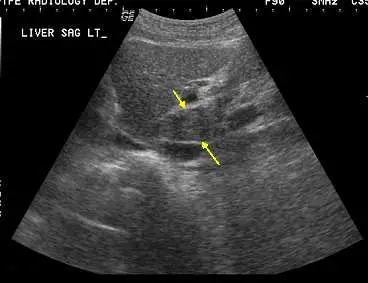

附圖為肝臟矢狀超音波掃描,箭號所指為何?

影像標示「LIVER SAG LT_」,為肝臟左側矢狀切面(sagittal section)超音波掃描。圖中可見兩個黃色箭號指向肝臟後內側一個相對獨立、回音較均勻的小葉狀結構,位於左葉後方、緊鄰下腔靜脈(inferior vena cava, IVC)前方。此結構在超音波影像上以靜脈韌帶裂(fissure for ligamentum venosum)與左葉分隔,前緣可見左側門靜脈(left portal vein),後緣鄰接 IVC,符合尾葉(caudate lobe / Couinaud segment I)的標準超音波影像表現。

尾葉為解剖學上獨立的肝葉,具有自己的門靜脈、肝動脈、膽管和肝靜脈引流,其靜脈直接匯入 IVC,不經由三條主要肝靜脈,這也是超音波矢狀掃描中辨識它的重要解剖依據。